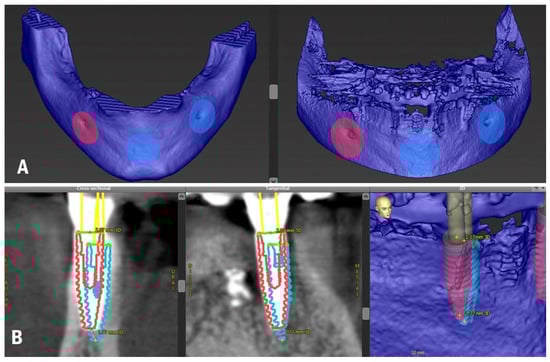

3.2. In Vitro Treatment Evaluation

In the in vitro evaluation, it was possible to apply both DICOM-to-DICOM and DICOM-to-STL matching protocols of the accuracy assessment techniques. Segmentation used for designing the bone-supported template was converted into an STL file and 3D printed with a Phrozen Sonic 4K printer, utilizing a mixture of a radiopaque polymer Dental RO (HARZ Labs) (60%) and transparent polymer Dental Clear (HARZ Labs) (40%) to reproduce the mandible not fully radiopaque and of a similar bone density. Four implants, identical to those placed in vivo, were inserted into the 3D-printed model of the mandible. The same protocol for s-CAIS and the same surgical template was used (Figure 3A).

Figure 3.

(A) In vitro implant placement; (B) CBCT of a 3D-printed mandible with inserted implants; (C) Planning and 3D-printed model CBCT matching; (D) Matching of implants in planning and implants placed in vitro; and (E) Accuracy analysis with the CBCT of the model.

A CBCT of the model was then performed (Figure 3B) followed by its matching with the preoperative CBCT (Figure 3C) to obtain data for the accuracy analysis of implant placement. Each implant was aligned in the preoperative and postoperative CBCT (Figure 3D). Accuracy values were automatically generated by the software (Figure 3E) and the results are reported in Table 2.

Four scan bodies were tightened onto the implants inserted in the model (Figure 4A), and a lab scanner (Straumann 7 series lab scanner, Institut Straumann AG) was used to obtain data in STL format.

Figure 4.

(A) Scan bodies mounted on the implants placed in vitro; (B) Planning CBCT and postoperative STL matching; (C) Accuracy analysis between STL file and scan bodies.

The STL file with the scan bodies was uploaded to the software and matched with the preoperative planning CBCT (Figure 4B). Each implant was matched in the preoperative CBCT and STL file by simply clicking on the top of the corresponding scan body. The matching was performed automatically compared to the CBCT method, otherwise, where it was performed manually by matching the anatomy of the implant, it became a user-dependent technique. Accuracy values were automatically generated by the software (Figure 4C) and the results are reported in Table 3.